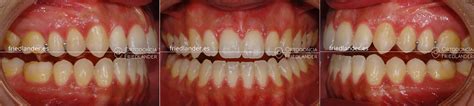

Después de unos 16 meses de tratamiento con brackets convencionales obtuvimos estos resultados.

Resultados después de 16 meses con ortodoncia fija y microtornillos

Comparación del antes y después del tratamiento

Antes y después del tratamiento